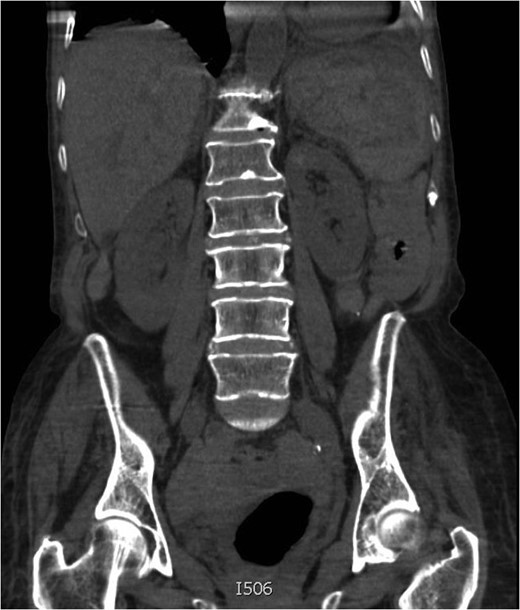

On Day 4, her haemoglobin had decreased to 64 g/dL. Her blood pressure and heart rate remained within normal parameters but a repeat clinical examination revealed a large peri-umbilical ecchymosis (Cullen's sign) (Figs 1 and 2). At this point, she was referred to the surgical team and a computed tomography (CT) scan confirmed a grade V splenic injury with overlying rib fractures, free fluid within the pelvis, but no active bleeding (Figs 3 and 4). The patient's Rivaroxaban was discontinued and Haematology advice was sought. The patient was transfused with packed red blood cells and managed non-operatively. The patient responded well to fluid and blood-product resuscitation, and since discussion with the Radiology team excluded active haemorrhage on the CT non-operative treatment was opted. Concurrent treatment was given for pneumonia and the patient was discharged on the 14th day. Rivaroxaban was re-commenced in the community on discharge following advice from the hospital Haematology team. A 24-h ECG and cardiology follow-up was arranged as an outpatient. Up to the current time of publication, her recovery has been unremarkable.